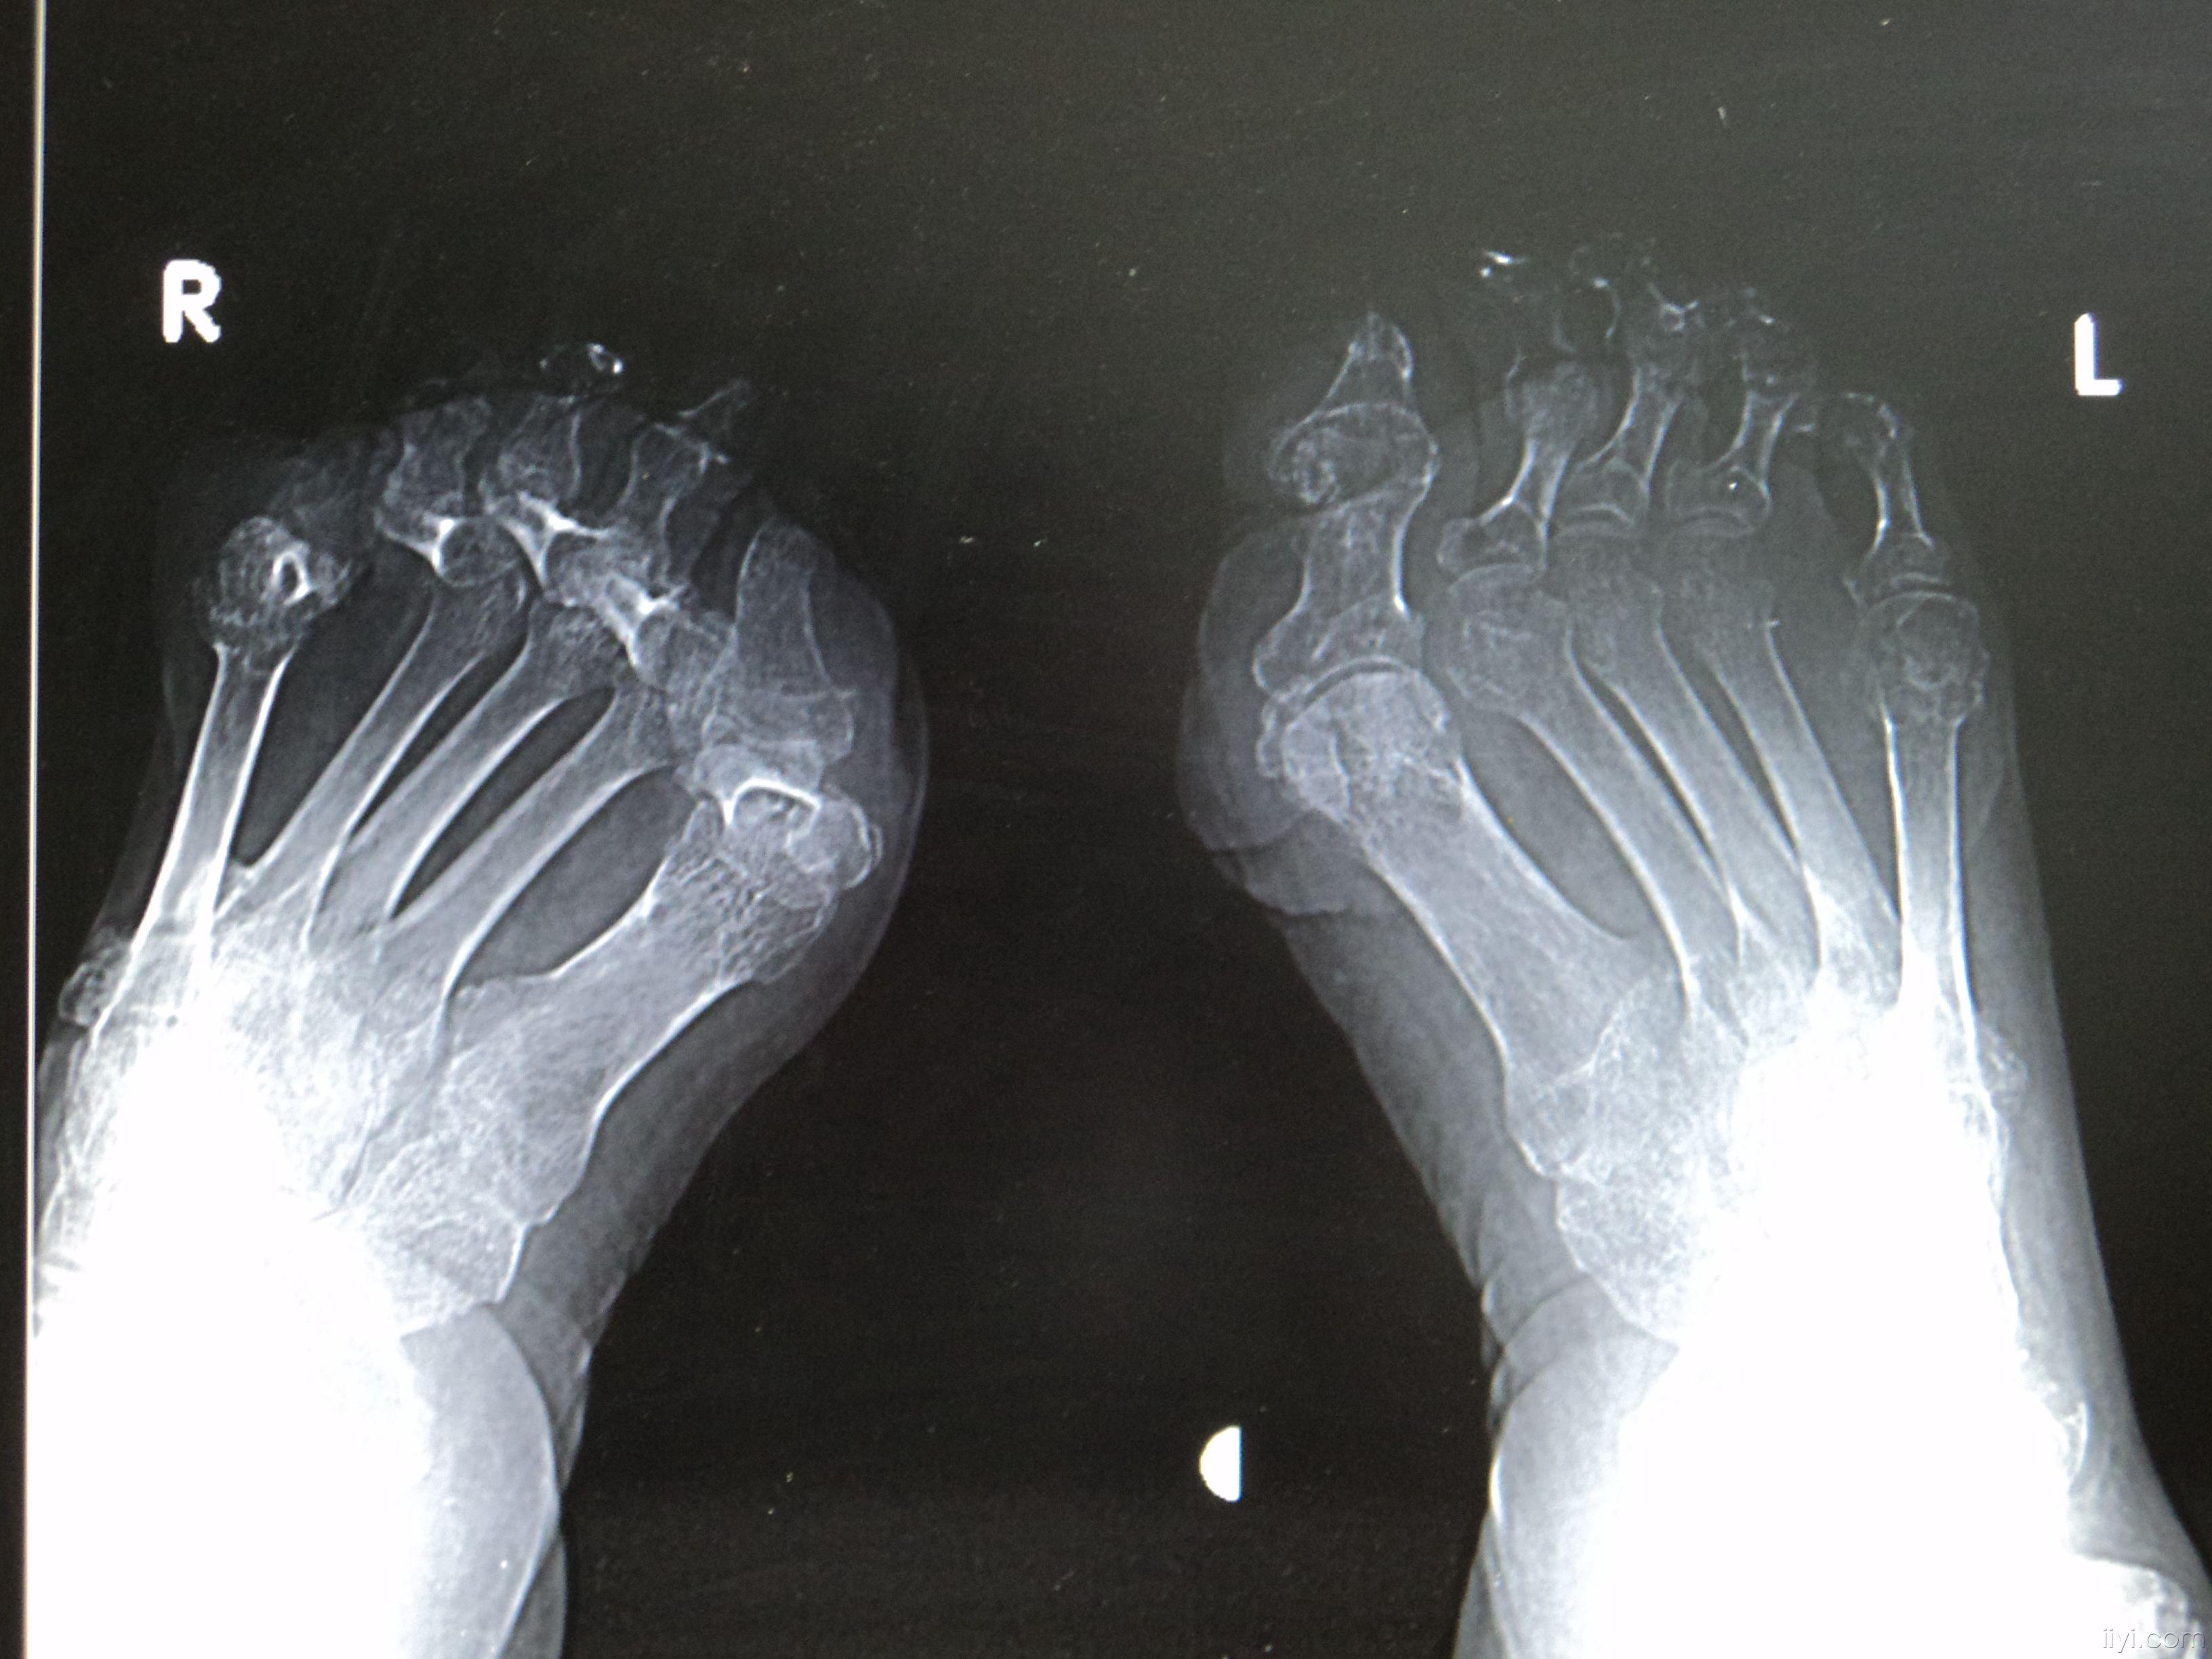

【读片】痛风性关节炎一例 [病例帖]

今天有幸见到少见的"麻风"病人的x线趾骨关节之影像

类风湿还是痛风?